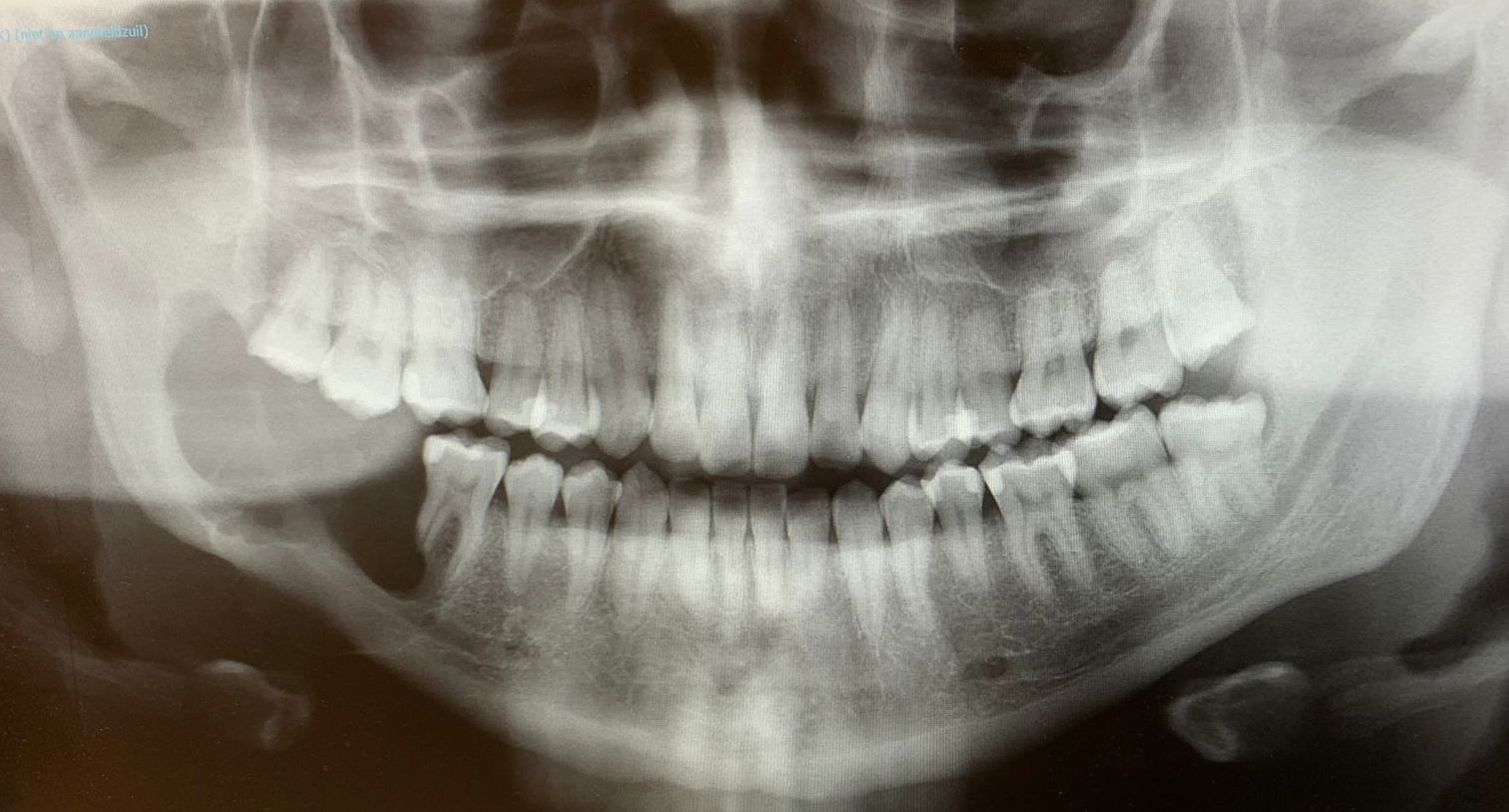

"I was at work when I received a call from the dentist asking if he could speak to me for a moment," recounts Timothy's mother, Usha Arends. The diagnosis was that Timothy had an Ameloblastoma. It's a tumor (benign but highly aggressive) that occurs exclusively in the jaw and affects only 0.92 people per million. Timothy was one of those 0.92 individuals. "It was a difficult moment for me and my family,"

Titi says. Nevertheless, he refused to let this new situation break him. With unwavering determination, within a week, instead of starting school, Titi was on a plane to Bucaramanga for his treatment. There, the diagnosis was confirmed. An urgent operation was needed to remove the tumor from his jaw, a long and painful process that required two Maxillofacial Surgeons.

"I wish the tumor never returned," Titi told his mother during the summer vacation of 2022. He began to feel the same symptoms in his jaw as he felt in 2019 when he was already attending school, but he chose not to say anything to avoid interrupting his studies. A doctor's examination confirmed his suspicion; the tumor had returned. This time, seeing that he had already gone through one surgery, the only option left was to undergo a mandibulectomy.

This involved removing his jaw, placing a titanium plate, and covering it with bone from his hip. In July 2022, Timothy was once again on a plane, this time heading to the Netherlands for tests that lasted a month. He returned to Aruba to resume school for a while, and at the end of October, he had to make another trip to the Netherlands for the surgery. The operation took almost 7 hours but was a complete success. Despite facing a serious infection during his recovery, Titi never complained or lost his spirits. "Even during the early morning when we had to rush to the emergency room because pus started coming out of his throat wound, Titi was still making jokes," his mother recalls.